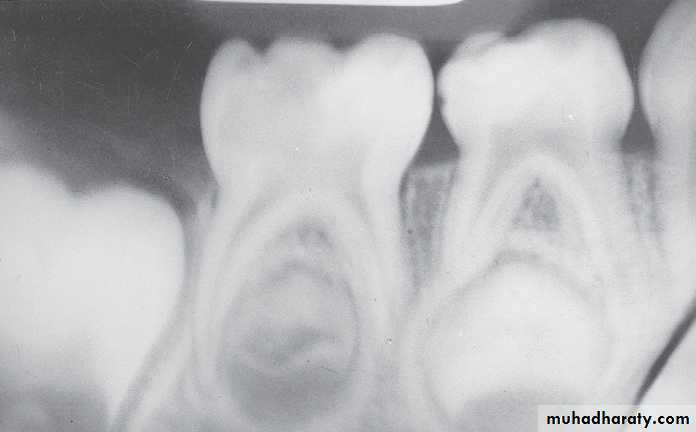

A, Pulp of the fi rst permanent molar was exposed by caries. The tooth was considered a candidate for the calcium hydroxide pulpotomy technique.

B, Calcifi ed

bridge has formed over the vital pulp in the canals.C, Continued

root development and pulpal recession are indicative of continuing pulpal vitality. The crown should be supported with a full-coverage restoration.Mature and immature teeth in the x-ray

Closed apex maxillary central incisors (mature)Open apex maxillary central incisors (immature)